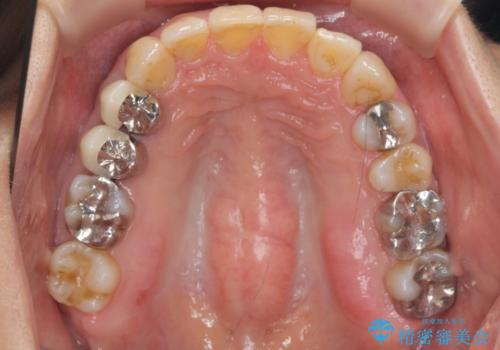

かみ合わせが深く、上の歯が咬みこんで下の歯にワイヤーがつけられない状態で、ワイヤー矯正はかなり難しい状態でした。

反対咬合や、すれ違い咬合もあり、大変難しいケースでしたが治療することができました。

かみ合わせが深い方はもともとかみしめが強く、マウスピース矯正を長期にすると、奥歯が咬まなくなってくる症状が強くなります。

今回もそういった状態になったのを、装着時間や歯の移動を工夫する形で治療しました。